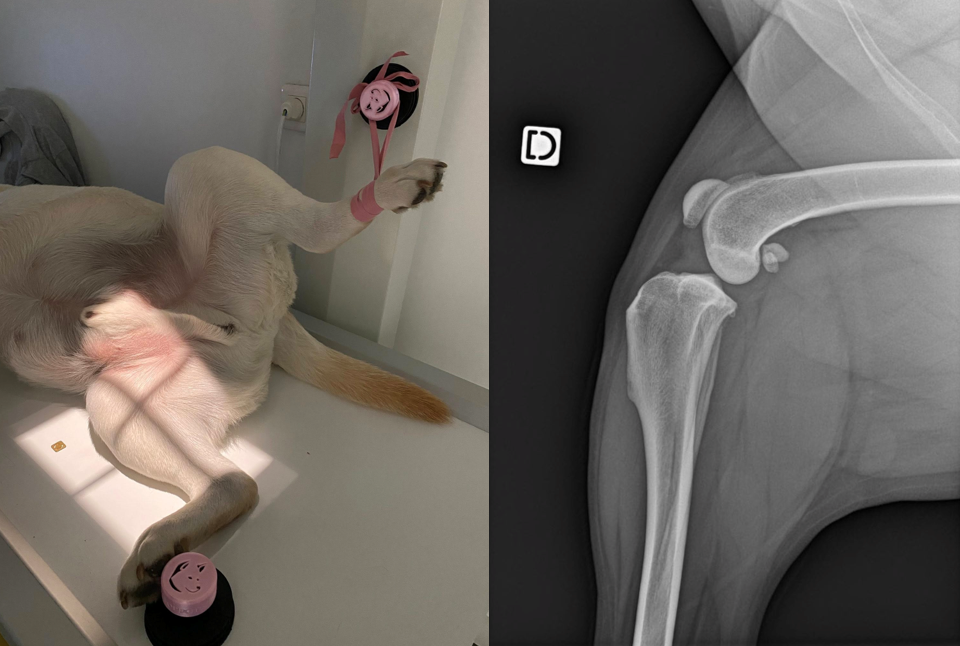

Zone visuel / vidéo

Ajoute ici une photo “en situation” (radiologie / table / bloc) ou un extrait de Reel.

Deux dispositifs phares pour améliorer la contention et la sécurité lors d’actes courants (radiologie, petites interventions, anesthésie…).

Ventouses + liens réutilisables pour stabiliser un animal sédaté sur une table lisse.

• Indications : radiologie, petites interventions, contention douce sous sédation.